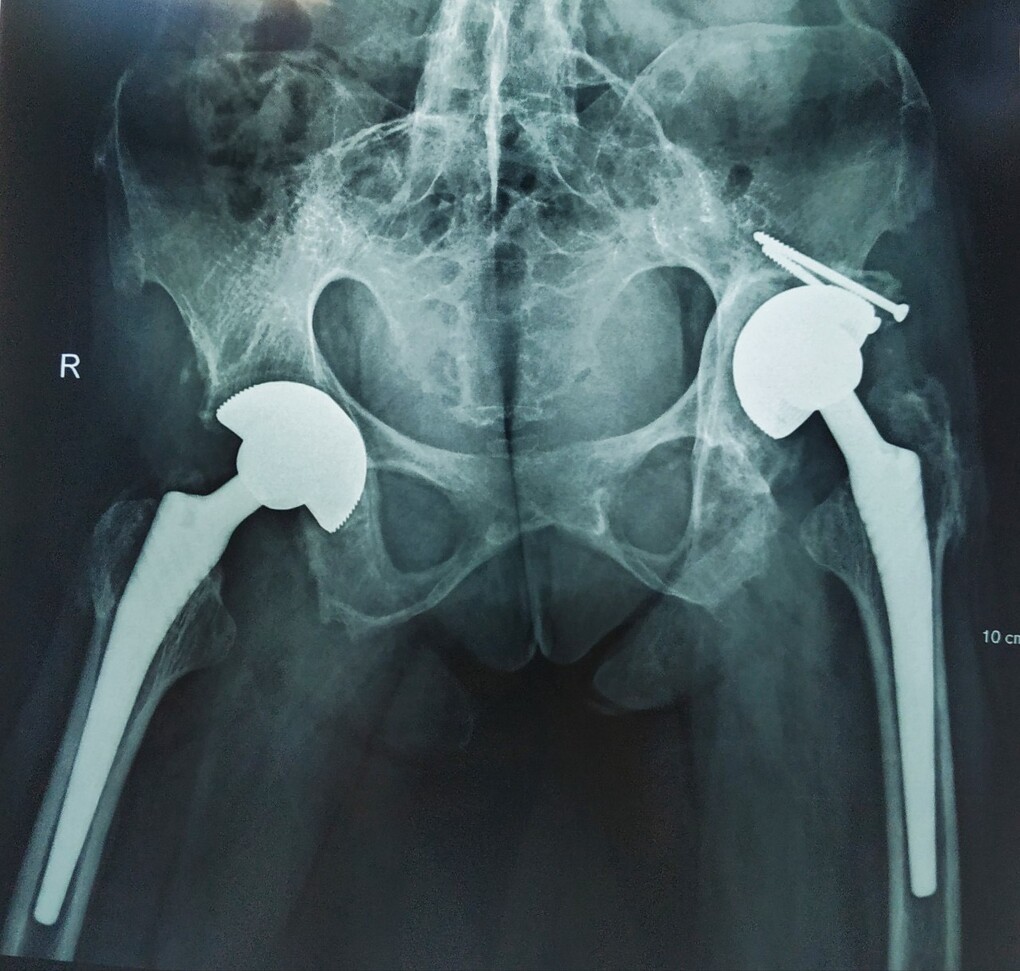

Bệnh nhân được thay hai khớp háng để có thể đi lại được. Ảnh: Bệnh viện cung cấp.

"Chúng tôi hội chẩn, quyết định mổ thay khớp háng 2 bên bằng kỹ thuật mổ ít xâm lấn với khớp hai chuyển động chống trật và chống mài mòn", bác sĩ Toàn nói.

Không có cách điều trị triệt để viêm cột sống dính khớp. Các phương pháp hiện nay chỉ có thể cải thiện triệu chứng và ngăn ngừa bệnh trở nên xấu đi. Phẫu thuật thay khớp háng chỉ định trong trường hợp bệnh nhân đau kéo dài, hạn chế vận động và có phá hủy cấu trúc rõ trên hình ảnh X-quang. Phẫu thuật chỉnh hình đối với cột sống khi cột sống biến dạng.